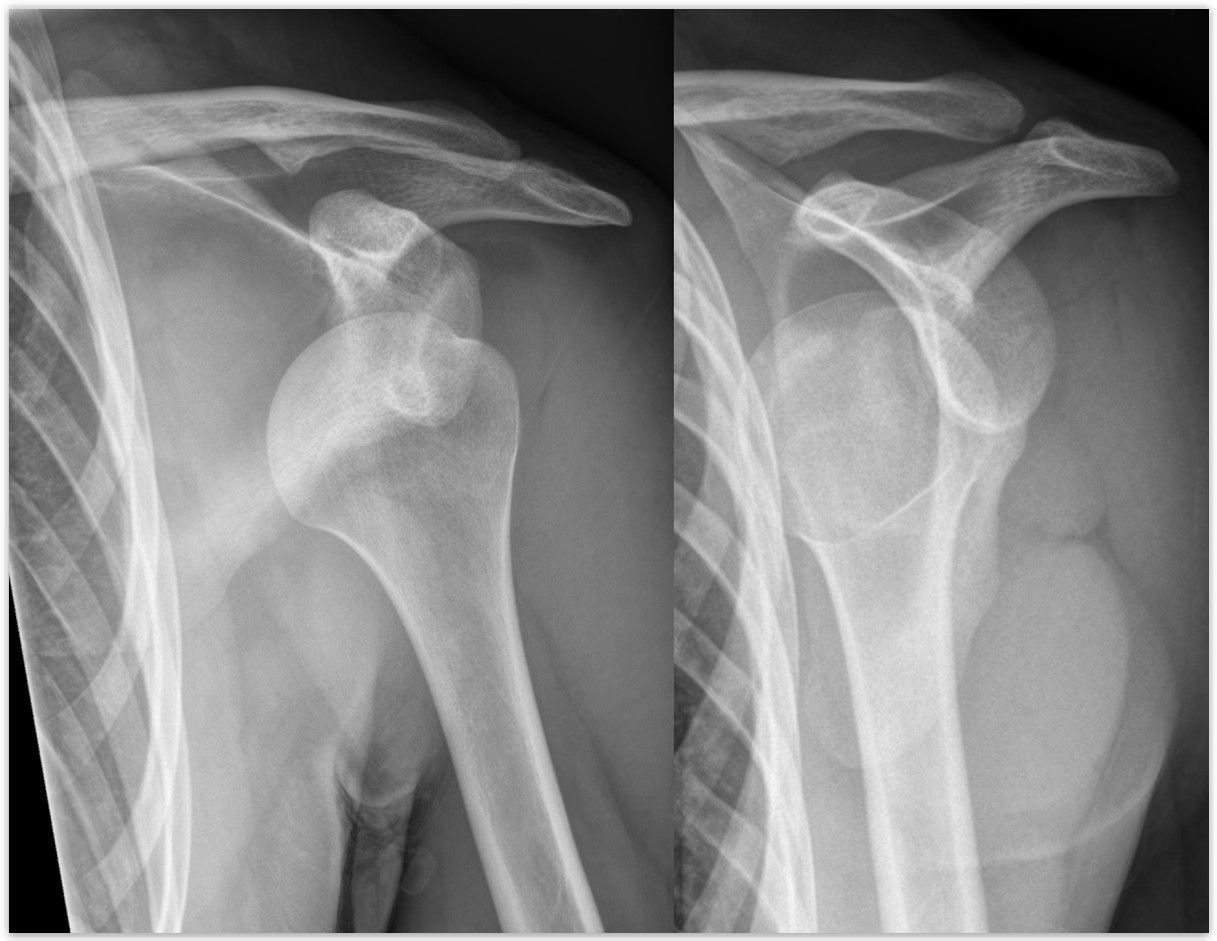

how does a GH Subluxations/Dislocations occur?

force on shoulder, can have anterior (most common), posterior, and inferior (rare) dislocations

GH Subluxations/Dislocations symptoms

A sublux will have pain, limited ROM, while a dislocation will have a deformity, pain, and no ROM

GH Subluxations/Dislocations treatment

If trained, reduce it and ship; if not, splint and ship

first time dislocation = always suspect a fracture

chronic inj. = may brace to reduce the chance, as the labrum is torn

person needs to keep up with a rehab plan, as the dynamic muscles are the best thing to keep the GH head in

bankart lesion

anterior defect of labrum

hill sachs lesion

divot in humeral head

what are complications of GH dislocations?

Hills sachs and bankart lesion

how are Hills Sachs and Bankart lesions treated?

surgeon will try to fix these is the GH patient ops for surgery to fix their labrum